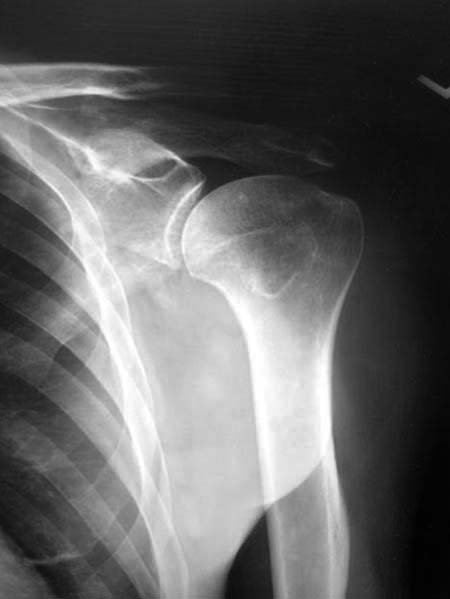

Данный перелом относится к перелому тело лопатки и несмотря на

наслоение, где лопатка покрывает грудную клетку, но можно увидеть три

большие фрагмента, которые находятся в разных плоскостях. Суставная

поверхность расположена намного медиальнее, что нарушает бланс мышц,

которая в последующем может привести к ограничению движения верхного

пояса. Расположение суставной поверхности нуждается в уточнении

дополнительными исследованиями, включая КТ и стандартные снимки плеча.!

Здесь пример, стандартные снимки: плечо и лопатка прямой снимок,

аксиллярный и косой снимки (Y-view) и фиксация пластинами по краям, где